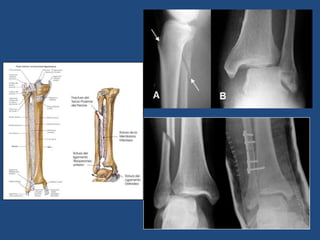

FRACTURAS DE TOBILLO

• Alta incidencia

• Ojo a las Fx-Lux: Lesión importante de

partes blandas

• Mención especial: Palpar peroné en toda

su longuitud (Maissoneuve, Dupuytren)

Clasificación Danis-Weber

Radiología

Dudas: Rx Oblicuas y/o Rx Rodilla

Tratamiento Quirúrgico

• Fracturas desplazadas e inestables

• Necesitan posición muy forzada para

reducción

• Fracturas bimaleolares

• Fracturas abiertas